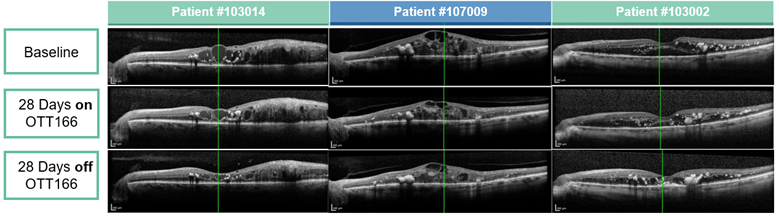

Optical Coherence Tomography (OCT) images from 3 patients with Diabetic Macular Edema (DME) demonstrating Central Retinal Thickness (CRT) improvement and a clear biologic effect of topical OTT-166

Patient #103014 #107009 #103002

Baseline 530   766   404.5

Day 28 327.5 -202.5 (-38%) 570 -196 (-25%) 288.5 -116 (-29%)

Day 56 267 -263 (-50%) 577 -189 (-25%) 243.5 -161 (-40%)

(note: central retinal thickness normal range: 260-280 µm)